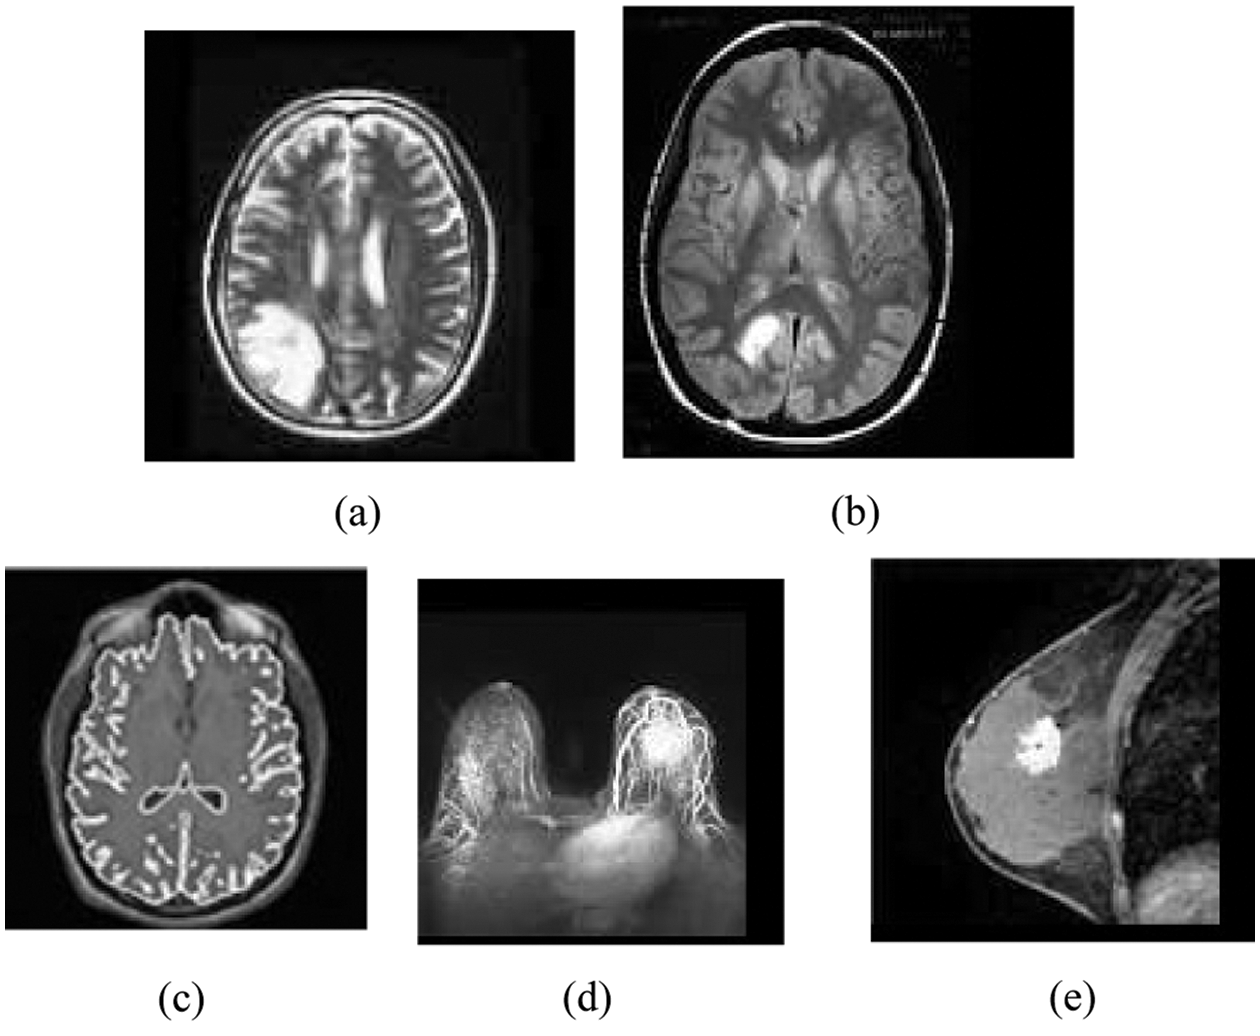

Figure 1: Original MR images: (a) Brain_1, (b) Brain_2, (c) Brain_3 (d) Breast_1 (e) Breast_2

A subset of this dataset containing ten sample standard MR brain and breast images via, Brain_1, Brain_2, Brain_3, Breast_1 and Breast_2 are reported as representative in this subsection. The sample MRI images are used in many research experiments as reported in (Lai & Huang 2011; Qi et al. 2015; Yong & Shuying 2007). Fig. 1 shows the five standard MRI gray scale images Brain_1, Brain_2, Brain_3, Breast_1 and Breast_2 as illustrated in Figs. 2a–2e respectively. In this experiment, each block of size (2 * 2) is considered as a vector and hence each sample image contains 3844, 4225, 3600, 3844 and 4225 vectors respectively.